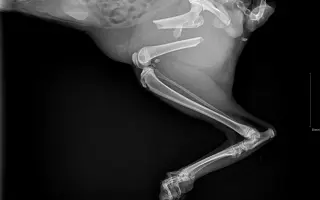

Fotogalerie